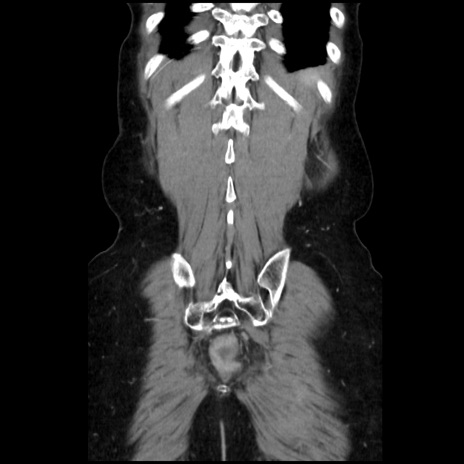

症例32(冠状断像)

症例

【症例】40歳代 女性

【主訴】上腹部痛、嘔気・嘔吐

【現病歴】約9時間前頃から急に上腹部痛、嘔気、嘔吐が出現。改善しないため救急要請。

【既往歴】子宮頚癌(広汎子宮全摘術、放射線療法)、腸閉塞

【身体所見】腹部:平坦、軟、腸雑音亢進、上腹部を中心に腹部全体に圧痛あり。

【データ】WBC 8400、CRP 0.03